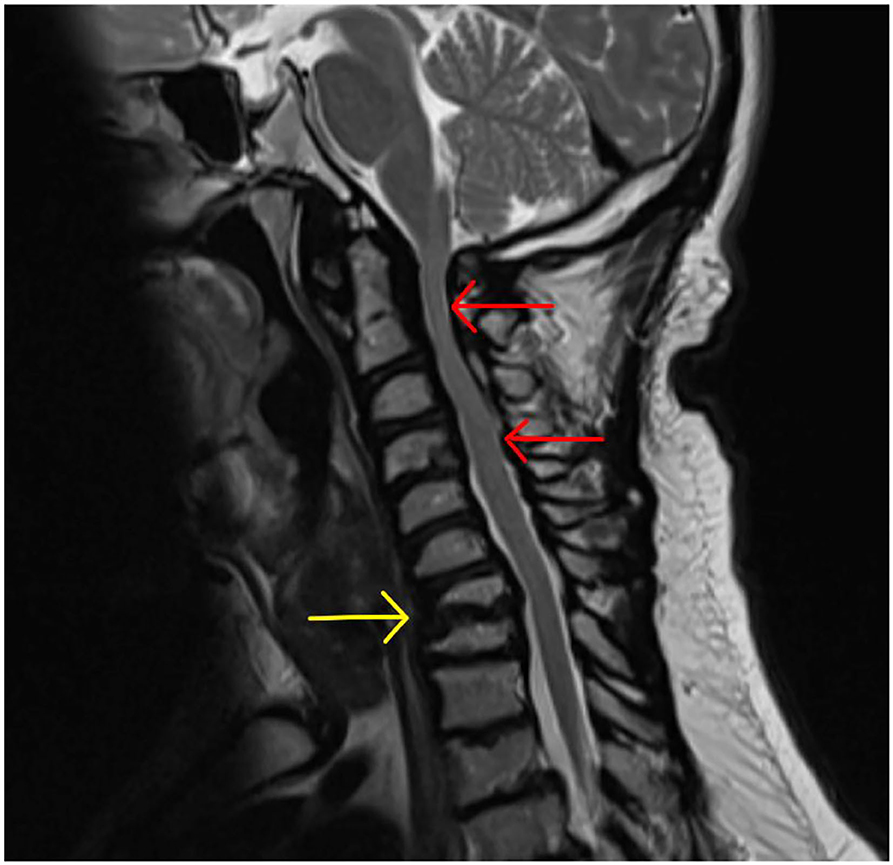

Cervical stenosis the most commonly occurring spinal pathology in MPS patients (MPS I, II, VI) and occurs due to accumulation of GAG in epidural connective tissue and ligamentum flavum plus the additional impact of hypoplastic posterior C1 arch and degenerative facet joints and intervertebral discs (207) (Figure 14).

Figure 14. Cervical cord stenosis. Sagittal MRI of adult with MPS I demonstrating cervical cord stenosis at C2–C4 and hypertrophied ligament, with effacement of anterior and posterior CSF spaces (red arrows). Also note the abnormal vertebrae at C7 and T1 with degenerative disc and hypertrophied ligament (yellow arrow) causing cervical-thoracic kyphosis and effacement of anterior CSF spaces.

Clinical manifestations depend on the anatomical level and severity of compression, but typically presents with numb, clumsy hands and difficulty with fine motor tasks. Carpal tunnel syndrome should be excluded in these instances, as this is also common in MPS I, II and III (217). Delayed presentation of cervical stenosis would present with a progressive myelopathy as in AAI (above), and has been reported in. 55% of adult MPS IVA patients (155).